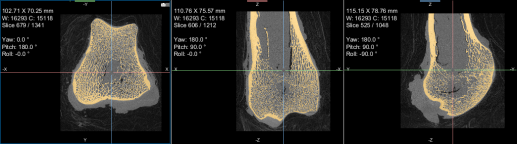

This section of the proximal femur tutorial describes how to compute high-resolution anisotropy maps in different orientations. You should note that when computing high-resolution maps, you should limit the volume of operation to regions that enclose only part of the region of interest. This can be done by creating a series of boxes that describe a particular orientation.

The images below (from left to right) correspond to XZ, XY, and oblique orientations. The computed vector fields are colored by magnitude.

High-definition vector field-based surface anisotropy maps

- Create a series boxes to enclose parts of the original region of interest.

You can resize and rotate the boxes, as well as change their position within a 2D or 3D view with the control points (see Editing Shapes).

- Adjust the boxes as follows:

- Choose the settings for each high-definition vector field-based surface anisotropy maps on the Mappings tab, as shown below.

NOTE You can decrease the sampling spacing and radius of influence to 0.0005 m and 0.0015 m, respectively, since you will be computing maps within a sub-volume.

- Click the Compute mapping button.

- Examine the results (see Examining the Computed Vector Field-Based Map).